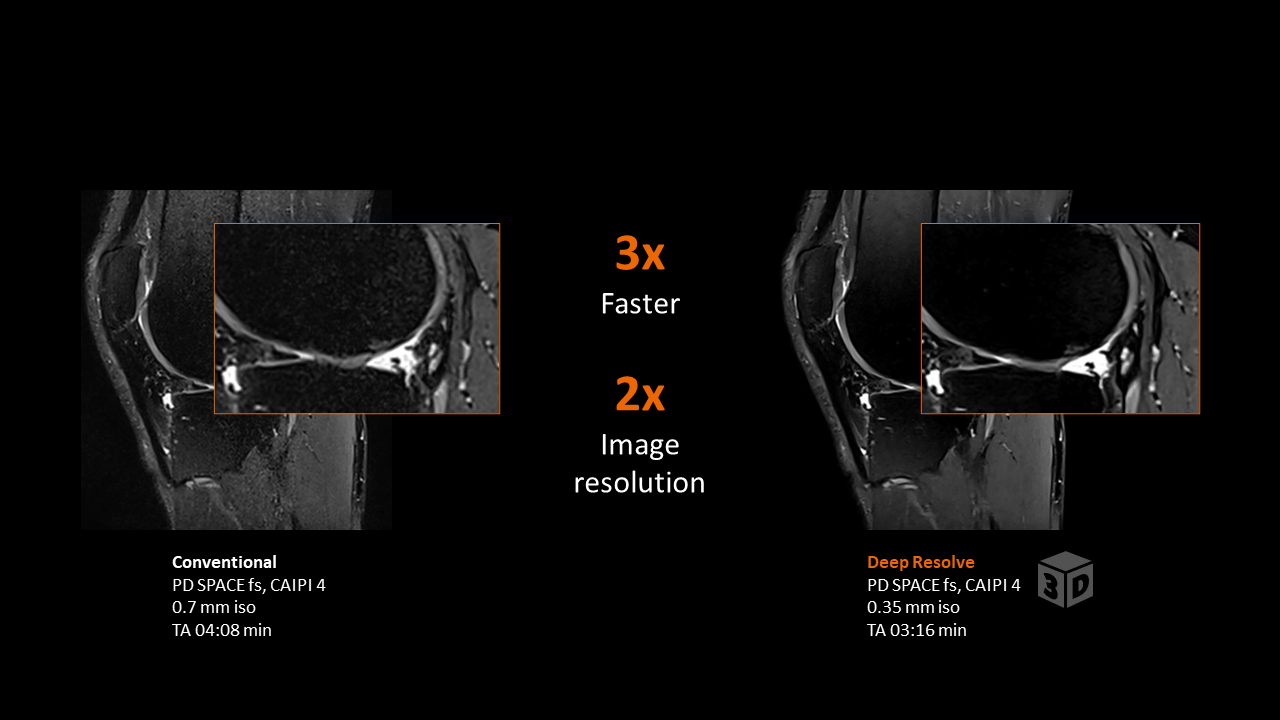

Klinische Beispielbilder

Bildquelle: Siemens Healthineers – MAGNETOM Sola